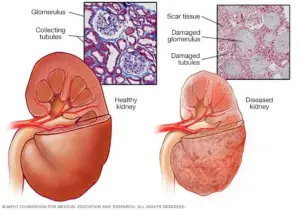

What Is Kidney Disease?

Kidney disease occurs when the kidneys lose their ability to function effectively. Causes include high blood pressure, diabetes, infections, autoimmune disorders, and genetic predispositions. Without proper treatment, kidney disease can progress to kidney failure, requiring dialysis or a transplant. Recognizing warning signs your kidneys are in danger can help you take action before it’s too late.